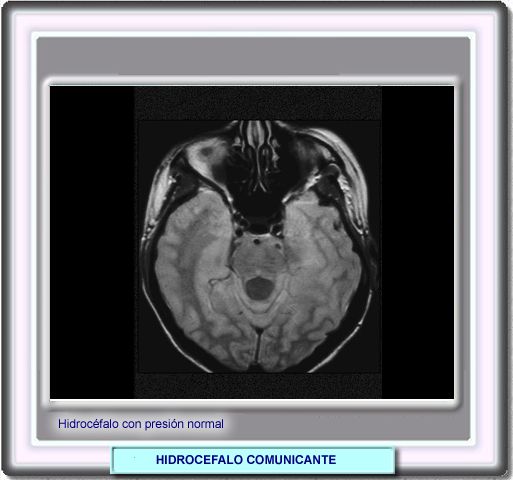

En los ancianos se produce un tipo de hidrocéfalo comunicante con una presión intraventricular normal. Esta forma de hidrocéfalo va acompaña de una triada clínica de demencia, trastornos de la marcha e incontinencia urinaria. Recibe el nombre de hidrocéfalo con presión normal